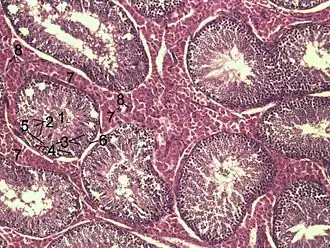

![]() Histological section through testicular parenchyma of a boar. 1 Lumen of Tubulus seminiferus contortus, 2 spermatids, 3 spermatocytes, 4 spermatogonia, 5 Sertoli cell, 6 myofibroblasts, 7 Leydig cells, 8 capillaries | |